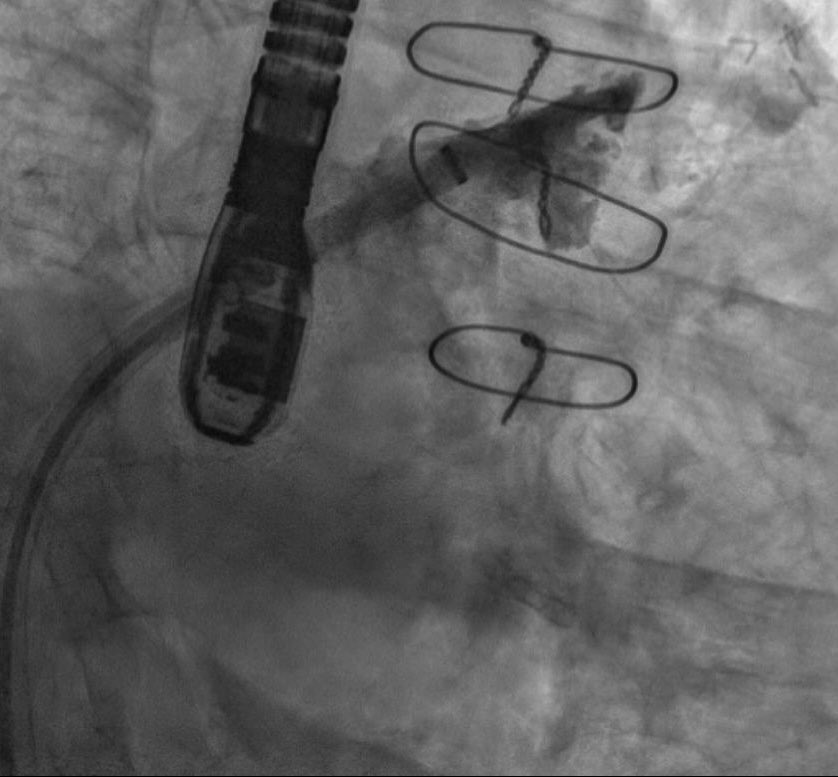

La versatilidad del dispositivo Watchman FLX permite cerrar orejuelas complejas como esta. Su pequeño tamaño supuso un reto pero finalmente conseguimos ocluirla con éxito. @GVAdsTorrevieja @CenturyRaul @bostonsci